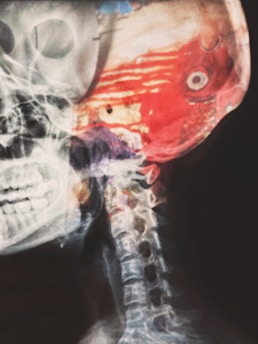

Stroke

A stroke occurs when blood flow to the brain is interrupted, leading to potential brain damage. Fast diagnosis and treatment are critical. We provide comprehensive stroke evaluations, prevention strategies, and recovery care to support brain health and minimize long-term effects.